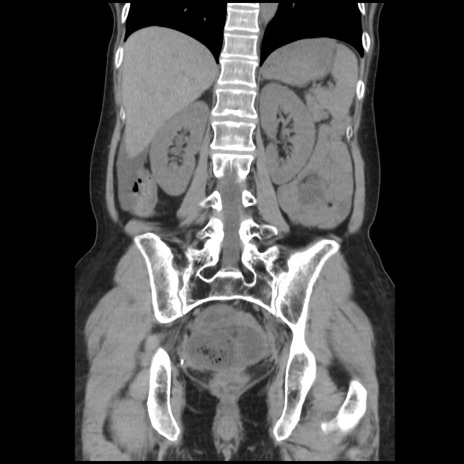

横断像

【症例】40歳代 女性

【主訴】上腹部痛、嘔気・嘔吐

【現病歴】約9時間前頃から急に上腹部痛、嘔気、嘔吐が出現。改善しないため救急要請。

【既往歴】子宮頚癌(広汎子宮全摘術、放射線療法)、腸閉塞

【身体所見】腹部:平坦、軟、腸雑音亢進、上腹部を中心に腹部全体に圧痛あり。

【データ】WBC 8400、CRP 0.03